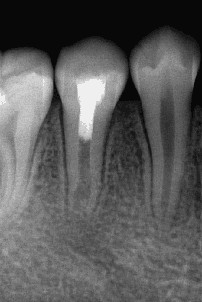

过牙髓再生治疗,促进牙髓坏死的年轻恒牙牙根进一步发育,牙髓活力测试呈阳性 。

术后3